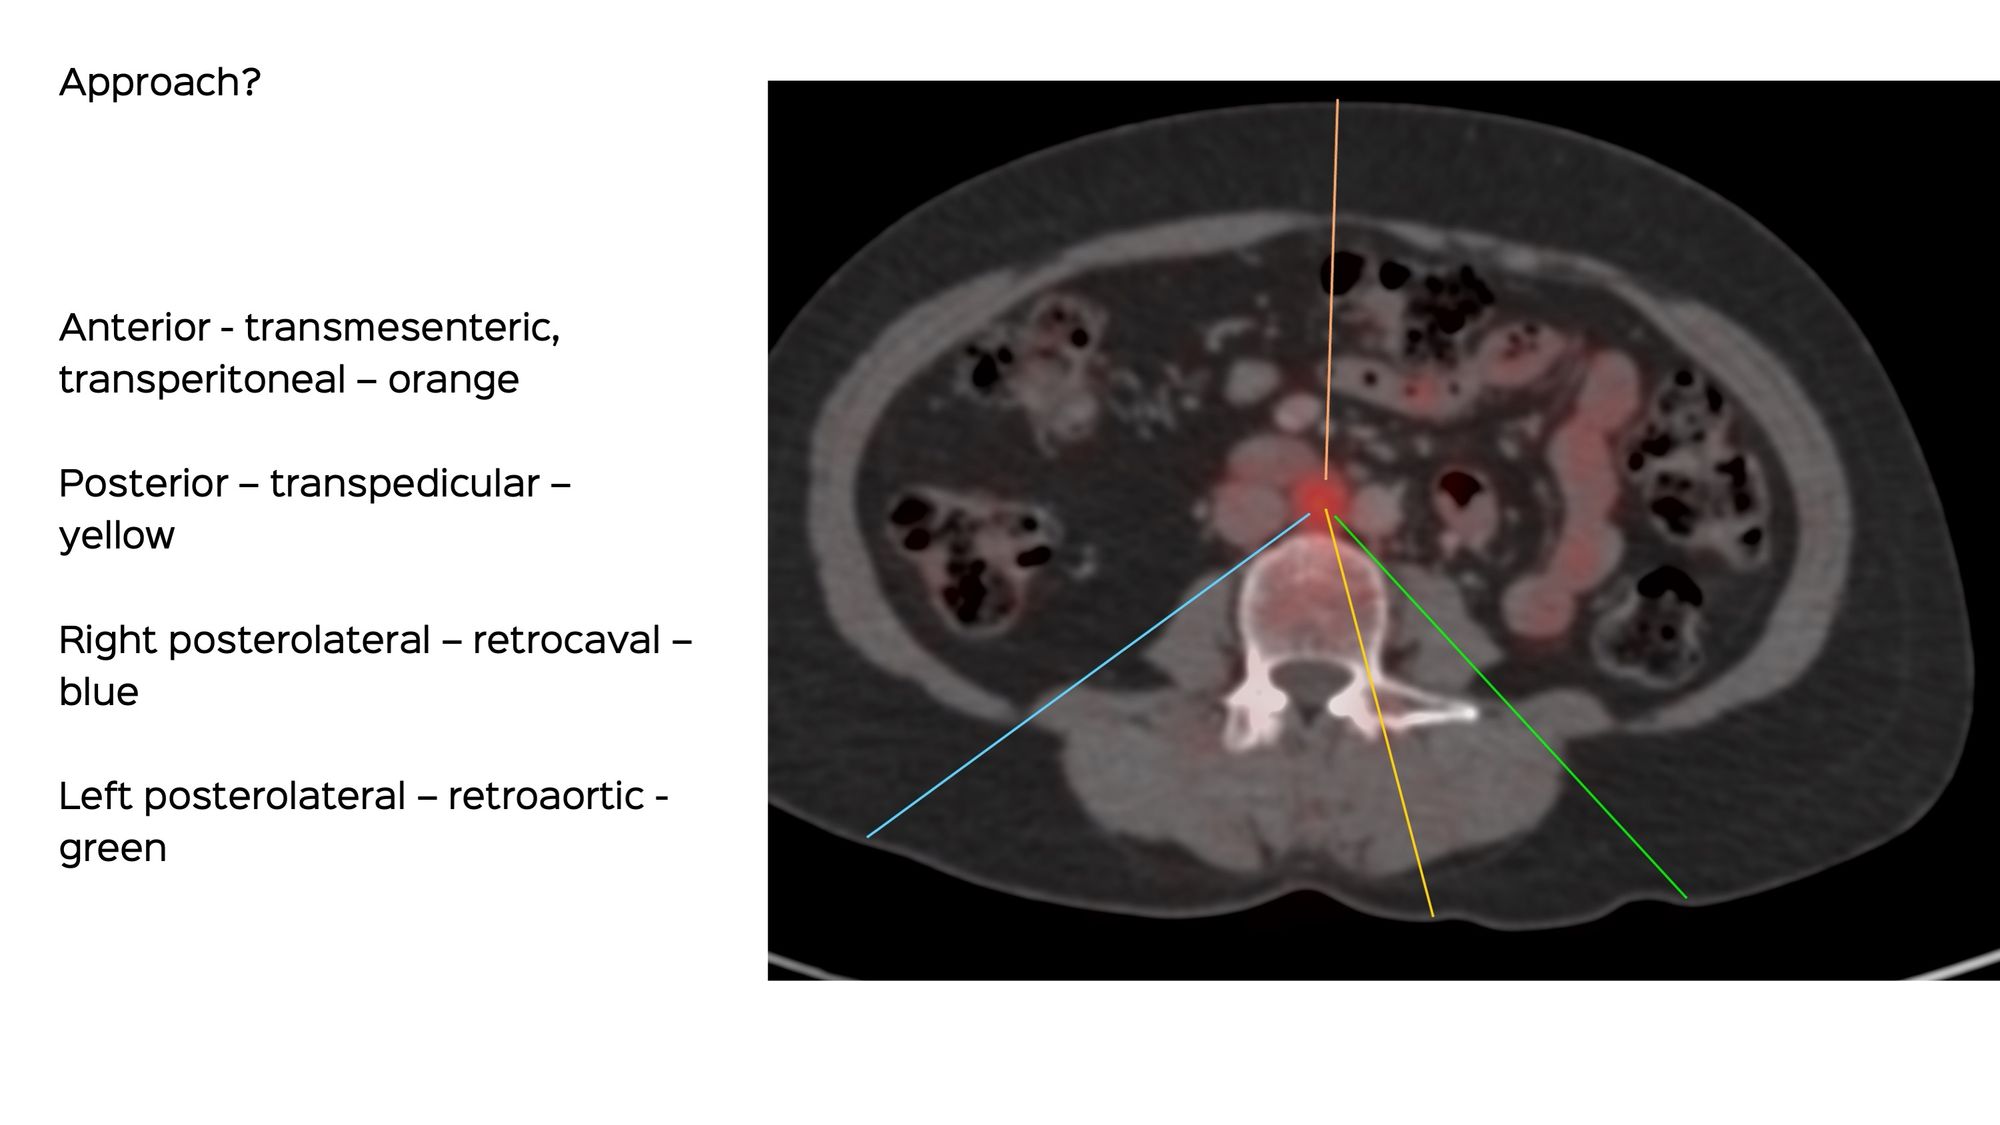

A 45-years old presented with new retroperitoneal nodes. The largest and most active was the aortocaval node.

The medical oncologist asked for a CT guided biopsy.

What route will you take?